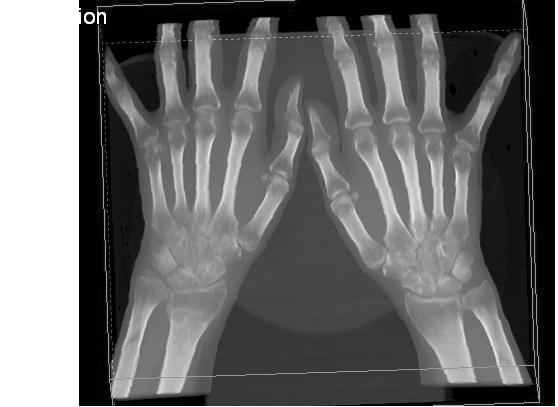

Уважаемые коллеги.Прошу обсудить случай лечения перелома дистального метаэпифиза лучевой кости. Ситуация скандальная и крайне неблагоприятная. Больная с патологической обстоятельностью мышления, склонностью к сутяжничеству, патологическими умозаключениями, не поддающимися коррекции (см. психиатрию, правда офиц. диагноза нет). В данном случае есть ряд ошибок с нашей стороны, прежде всего в отношении качества ведения документации (за что получил административное взыскание, по делом мне дураку). В остальном- придерживались в лечении подхода классический советской школы. Так как умную операцию…… сами знаете… 15.12- перелом луча в Москве. Там же репозиция, гипс. Дальнейшее лечение у нас в ЦРБ. 20.12.- вторичное смещение в гипсе21.12- под внутривенным наркозом- репозиция, гипсовая лонгета. Дальше начинается самое интересное. После репозиции больная заявила, что я (репозицию делал я) порвал ей все связки в суставе, посинел у нее 5 палец, якобы я за него тянул и т. д. На самом деле на 2 сутки после репозиции рука немного отекла и было незначительное сдавление гипсом, который был ослаблен. Дальнейшее лечение консервативное. Через 6 недель- гипс снят, назначено ЛФК. Пациентка крайне недовольна. Говорит, что на снимке у нее выступает кость, я ей сломал руку и.т.д. В общем началось. Пациентка прочитала в интернете наверное все, что есть по данной травме.По заключениями рентгенологов и консультанта из КДЦ областной больницы - стояние отломков допустимое. Объективно говоря- снижена высота лучевой кости, диастаз лучелоктевого сочленения, и не сросся шиловидный отросток. однако на РКТ при сравнении с другой стороной- разница незначительная. Дальше в одной из больниц нашей области и одной из больниц Москвы (вроде бы КГБ 53) врачи сказали, что репозиция сделана плохо. Нужна операция (восстановить длину лучевой кости), даже один из них предложил РЕДРЕССАЦИЮ (хи-хи) с наложением аппарата Илизарова. Что это для данной больной- радость неописанная. (см. описание психического статуса). Ничем другим, кроме зарабатывания дешевого авторитета объяснить данный факт не могу.Кстати, у больной еще нейропатия локтевого нерва.Для разрешения конфликта больная направлена на консультацию в ЦИТО на 03.03.11.

Я прекрасно знаю, что укорочение лучевой кости более 2 мм требует оперативного лечения с целью восстановления её длины, и что некоторые выполняют рефиксацию шиловидного отростка. (благо на последнем симпозиуме АО я присутствовал)

2.Укорочение лучевой кости и лучелоктевой диастаз невелики,но отрицать их клиническую значимость весьма сложно.

3.Исходя из конкретной ситуации и здравого смысла абсолютных показаний к операции не было и сразу после травмы и нет сейчас ,уже после сращения,поскольку перелом внесуставной,а осколок по тылу луча не препятствует торцевому упору по волярному краю луча.